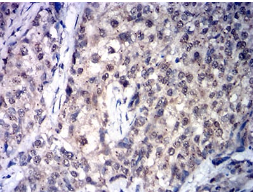

IHC    1/200 - 1/1000